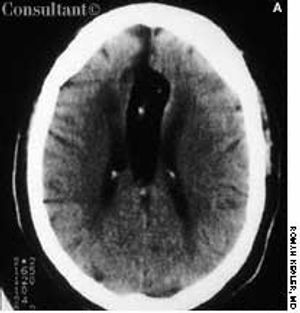

A 62-year-old African American woman was brought to the emergency department (ED) after the sudden onset of slurred speech and weakness in her left arm and leg. Her medical history included hypertension, insulin-dependent diabetes, and congestive heart failure.